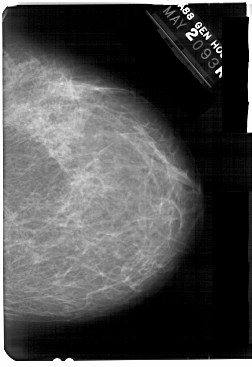

A_1369_1.LEFT_MLO

LEFT_MLO LINES 5491 PIXELS_PER_LINE 3781 BITS_PER_PIXEL 12 RESOLUTION 43.5 OVERLAY